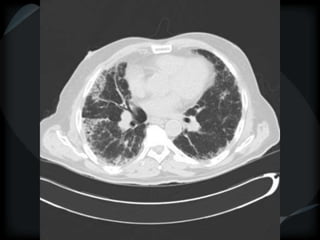

Airspace Patterns

 Inter and intralobular septal thickening / ground glass/crazy paving

Crazy paving